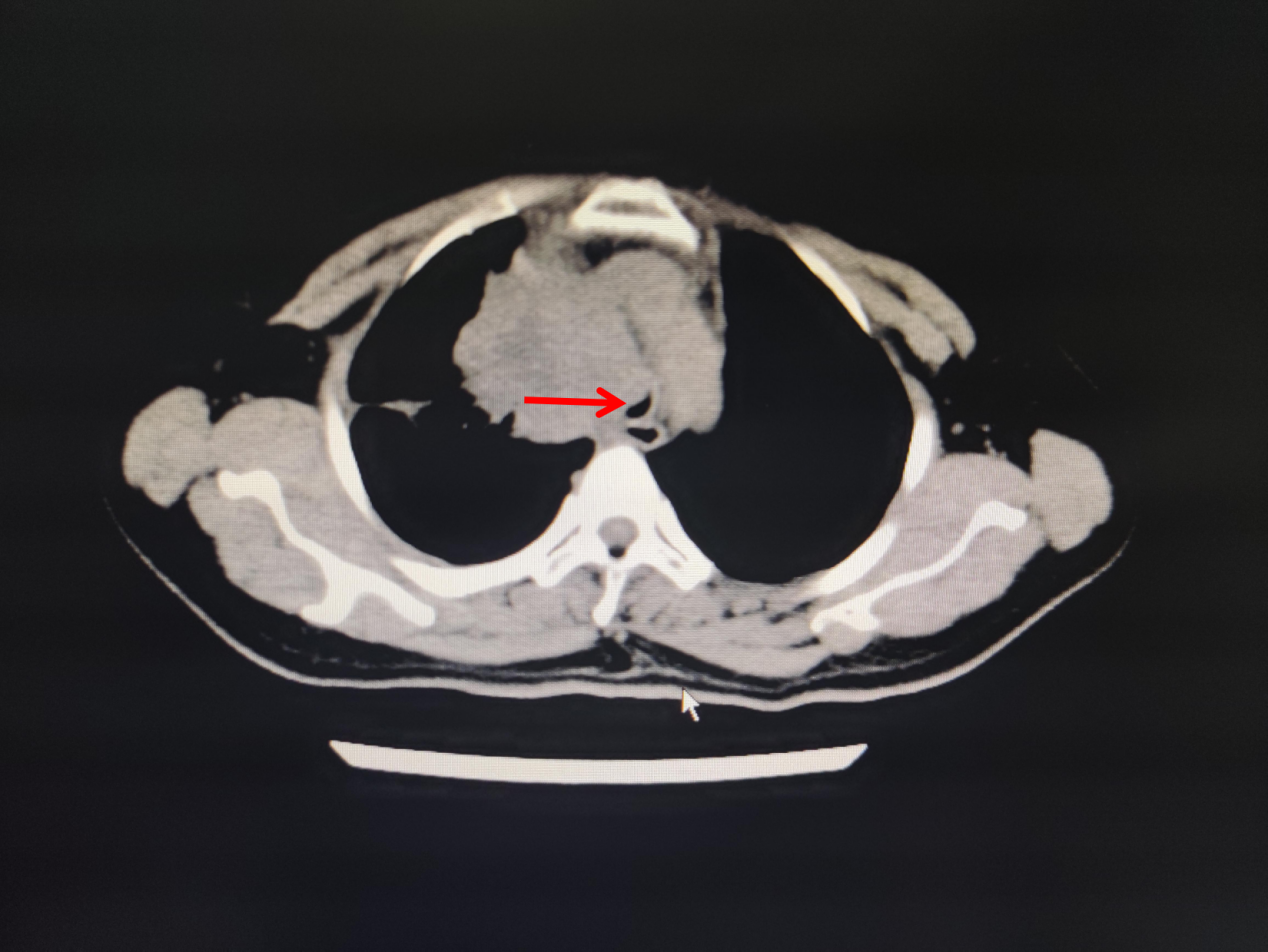

今年57岁的蔡女士,因晚期肺癌住院,肿瘤压迫气管导致气管严重狭窄,住院期间突发呼吸困难,伴烦躁不安、大汗淋漓,紧急行气管插管接呼吸机辅助通气,送ICU抢救。无独有偶,这边ICU医生正在积极抢救蔡女士,那边医院急诊科又打电话说急诊室有一名呼吸困难的患者需要紧急插管。这也是一名肿瘤压迫气管导致气管狭窄的患者,胸部CT可见气管中下段显著性狭窄,患者呼吸困难已近1周,今天突然加重,喘憋、口唇紫绀,ICU翁医生马上紧急予以气管插管,呼吸机持续性辅助通气。

图1.林某某CT 图2.蔡某某CT图片

两名患者行气管插管,接呼吸机辅助呼吸后,病情稍稳定,我院内镜中心呼吸介入治疗团队与ICU治疗团队立即组织病例讨论,行床边气管镜检查,发现两名患者气管均严重狭窄,最窄处不到0.5cm(正常成年人气管直径约1.5cm),一口痰都有可能导致患者严重窒息。在庄武主任和朱坤寿主任支持下,并请有关专家会诊,内镜中心呼吸内镜介入治疗团队经充分论证,认为唯一的治疗方法是——急诊全麻下经硬质气管镜硅酮支架置入术,利用硅酮支架的支撑力,扩张气管,解除呼吸道梗阻,否则患者随时存在生命危险,无法脱离呼吸机。